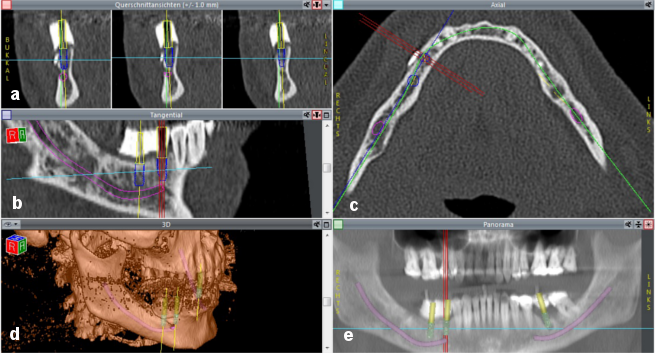

Implant planning and simulation were performed with CoDiagnostiX software (version 6.0, IVS Solutions AG, Chemnitz, Germany). CT data (in DICOM format) were imported into the software, which was then used to virtually place implants into their position and to assess them in multiplanar (axial, coronal and sagittal) and three-dimensional views. In addition, a pseudo-panoramic radiograph was created (Figure 6a-e [Fig. 6]).

Figure 6: Screenshot demonstrating implant planning a) coronal view; b) sagittal view; c) axial view; d) 3D view; e) pseudo-panoramic radiograph. The purple line demonstrates the inferior alveolar nerve. The blue cylinders represent the implants selected from the implant library. The yellow cylinders show the virtual abutments, which allow the implants to be placed in relation to the planned positions of the abutments. This allows an adequate prosthetic restoration to be achieved on the basis of the principle of backwards planning. Once the set-up was completed, the scan template was filled with barium sulfate. The planned location of the abutments was created in the template with a pilot drill. The green line (c) represents the panoramic curve, which allows a pseudo-panoramic radiograph to be generated. The yellow lines (a, b and d) show the vertical axis of the implant. The light blue lines show the horizontal axis of the implant. The three red lines (b, c and e) represent the axes of the implant that is being positioned.